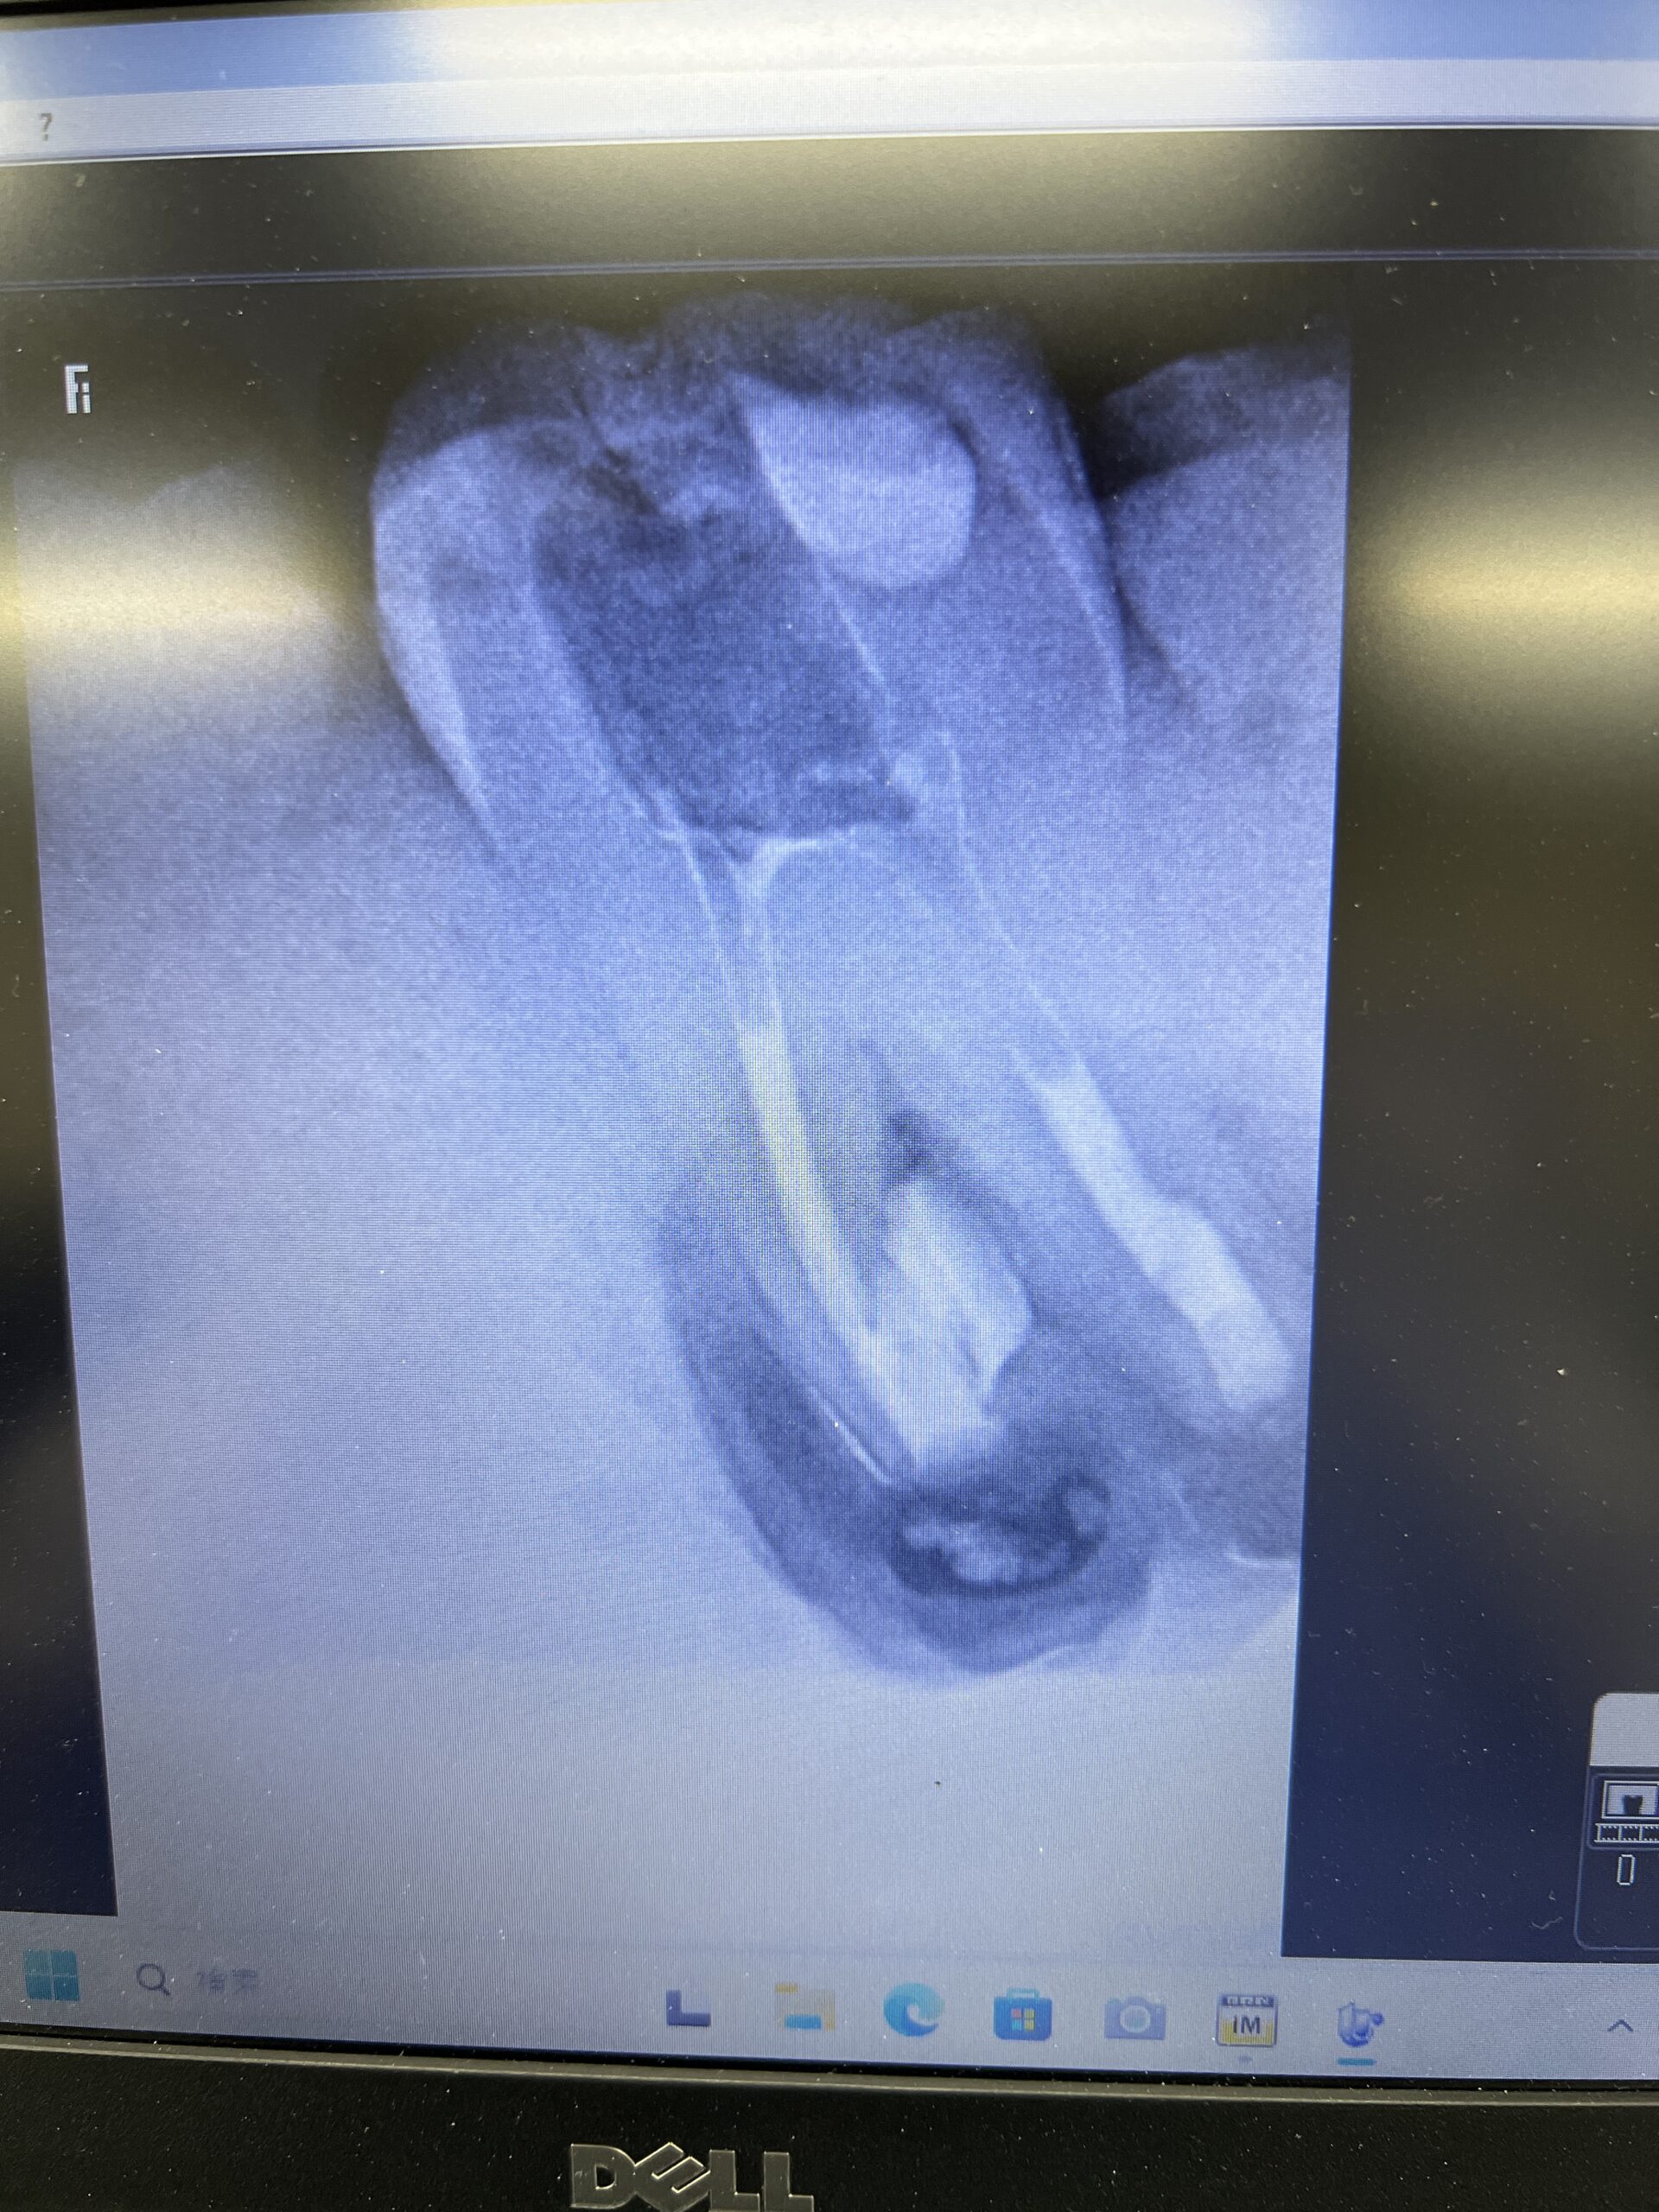

ここで、撮影をしてもらったCBCTを公開しよう。以下である。

これは私なら、もっと切断してやり直すだろう。

絵が、しょっぱいからだ。